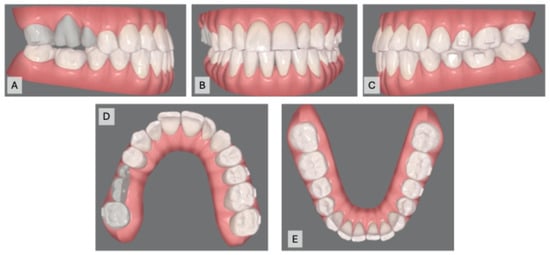

The patient was seen for visit 1 for transitional aligners 1–3 (3 weeks). At visit 2, an IPR of 0.3 for mandibular anterior teeth was performed, and aligners 4–15 (12 weeks) were provided. In visit 3, aligners 16–27 (12 weeks) were given, followed by 28–39 (12 weeks) at visit 4. The patient was instructed to change aligners weekly. Teeth tracking was satisfactory at each visit, with no emergency incidents or attachment breakage, and aligners adapted well to the M-PCA (Figure 10A–E).

Figure 10.

Intraoral photographs after orthodontic treatment: (A) right occlusion; (B) front occlusion; (C) left occlusion; (D) maxillary occlusion; (E) mandibular occlusion.